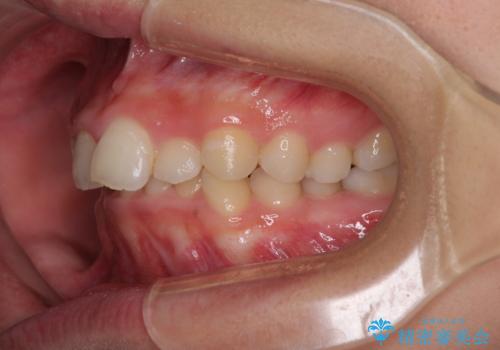

- 前歯の歯並びと不自然な色をした前歯のクラウンを気にして来院された患者様です。

上下前歯の歯列不正はインビザラインにより歯列を整え、その後に、前歯をオーダーメイドタイプのオールセラミッククラウンにて補綴治療することとしました。

前歯のデコボコを一番気にしていらっしゃいましたが、矯正治療により下顎前歯が隠れるほどのディープバイトも一緒に改善され、奥歯に負担のかかりにくい咬み合わせとなりました。